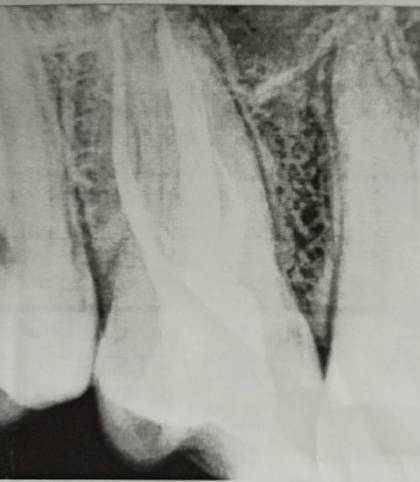

Здравствуйте, беспокоит уже несколько месяцев депульпированный зуб: ноет, воспаляется на горячее, периодически может под ночь постреливать в область глаза, а месяц назад (после того как врач в виду моих жалоб на ноющую боль перепломбировал какие-то из каналов неизвестно зачем) начала беспокоить периодическая пульсация в виске/над бровью (без боли, висок и в области тройничного нерва возле уха как бы немного сжимается/отекает или немеет), реагирует на постукивание и накусывание. Ушел от стоматолога, который его делал и обращался еще к двум, но ответ один - на снимке ничего толком не видно, будет дальше беспокоить - удаляйте и ставьте имплант.

Вчера сделал КТ и стало понятно, что в двух корнях выведен материал за верхушку что аж у корней шляпки появились, а другой корень недопломбирован до конца на несколько миллиметров. Я читал что материалы выводить за апекс в принципе нельзя и это чревато, неужели пульсация над бровью и в области виска связана с этим? Он же и после удаления зуба там останется, как я понял. Где этот материал находится судя по снимкам? Не может ли он как-то влиять на тройничный нерв (не разбираюсь с этим)?

Подскажите, пожалуйста, что тут можно сделать и насколько опасен этот выведенный материал. Вроде бы пломбировали Thermafil AH+.